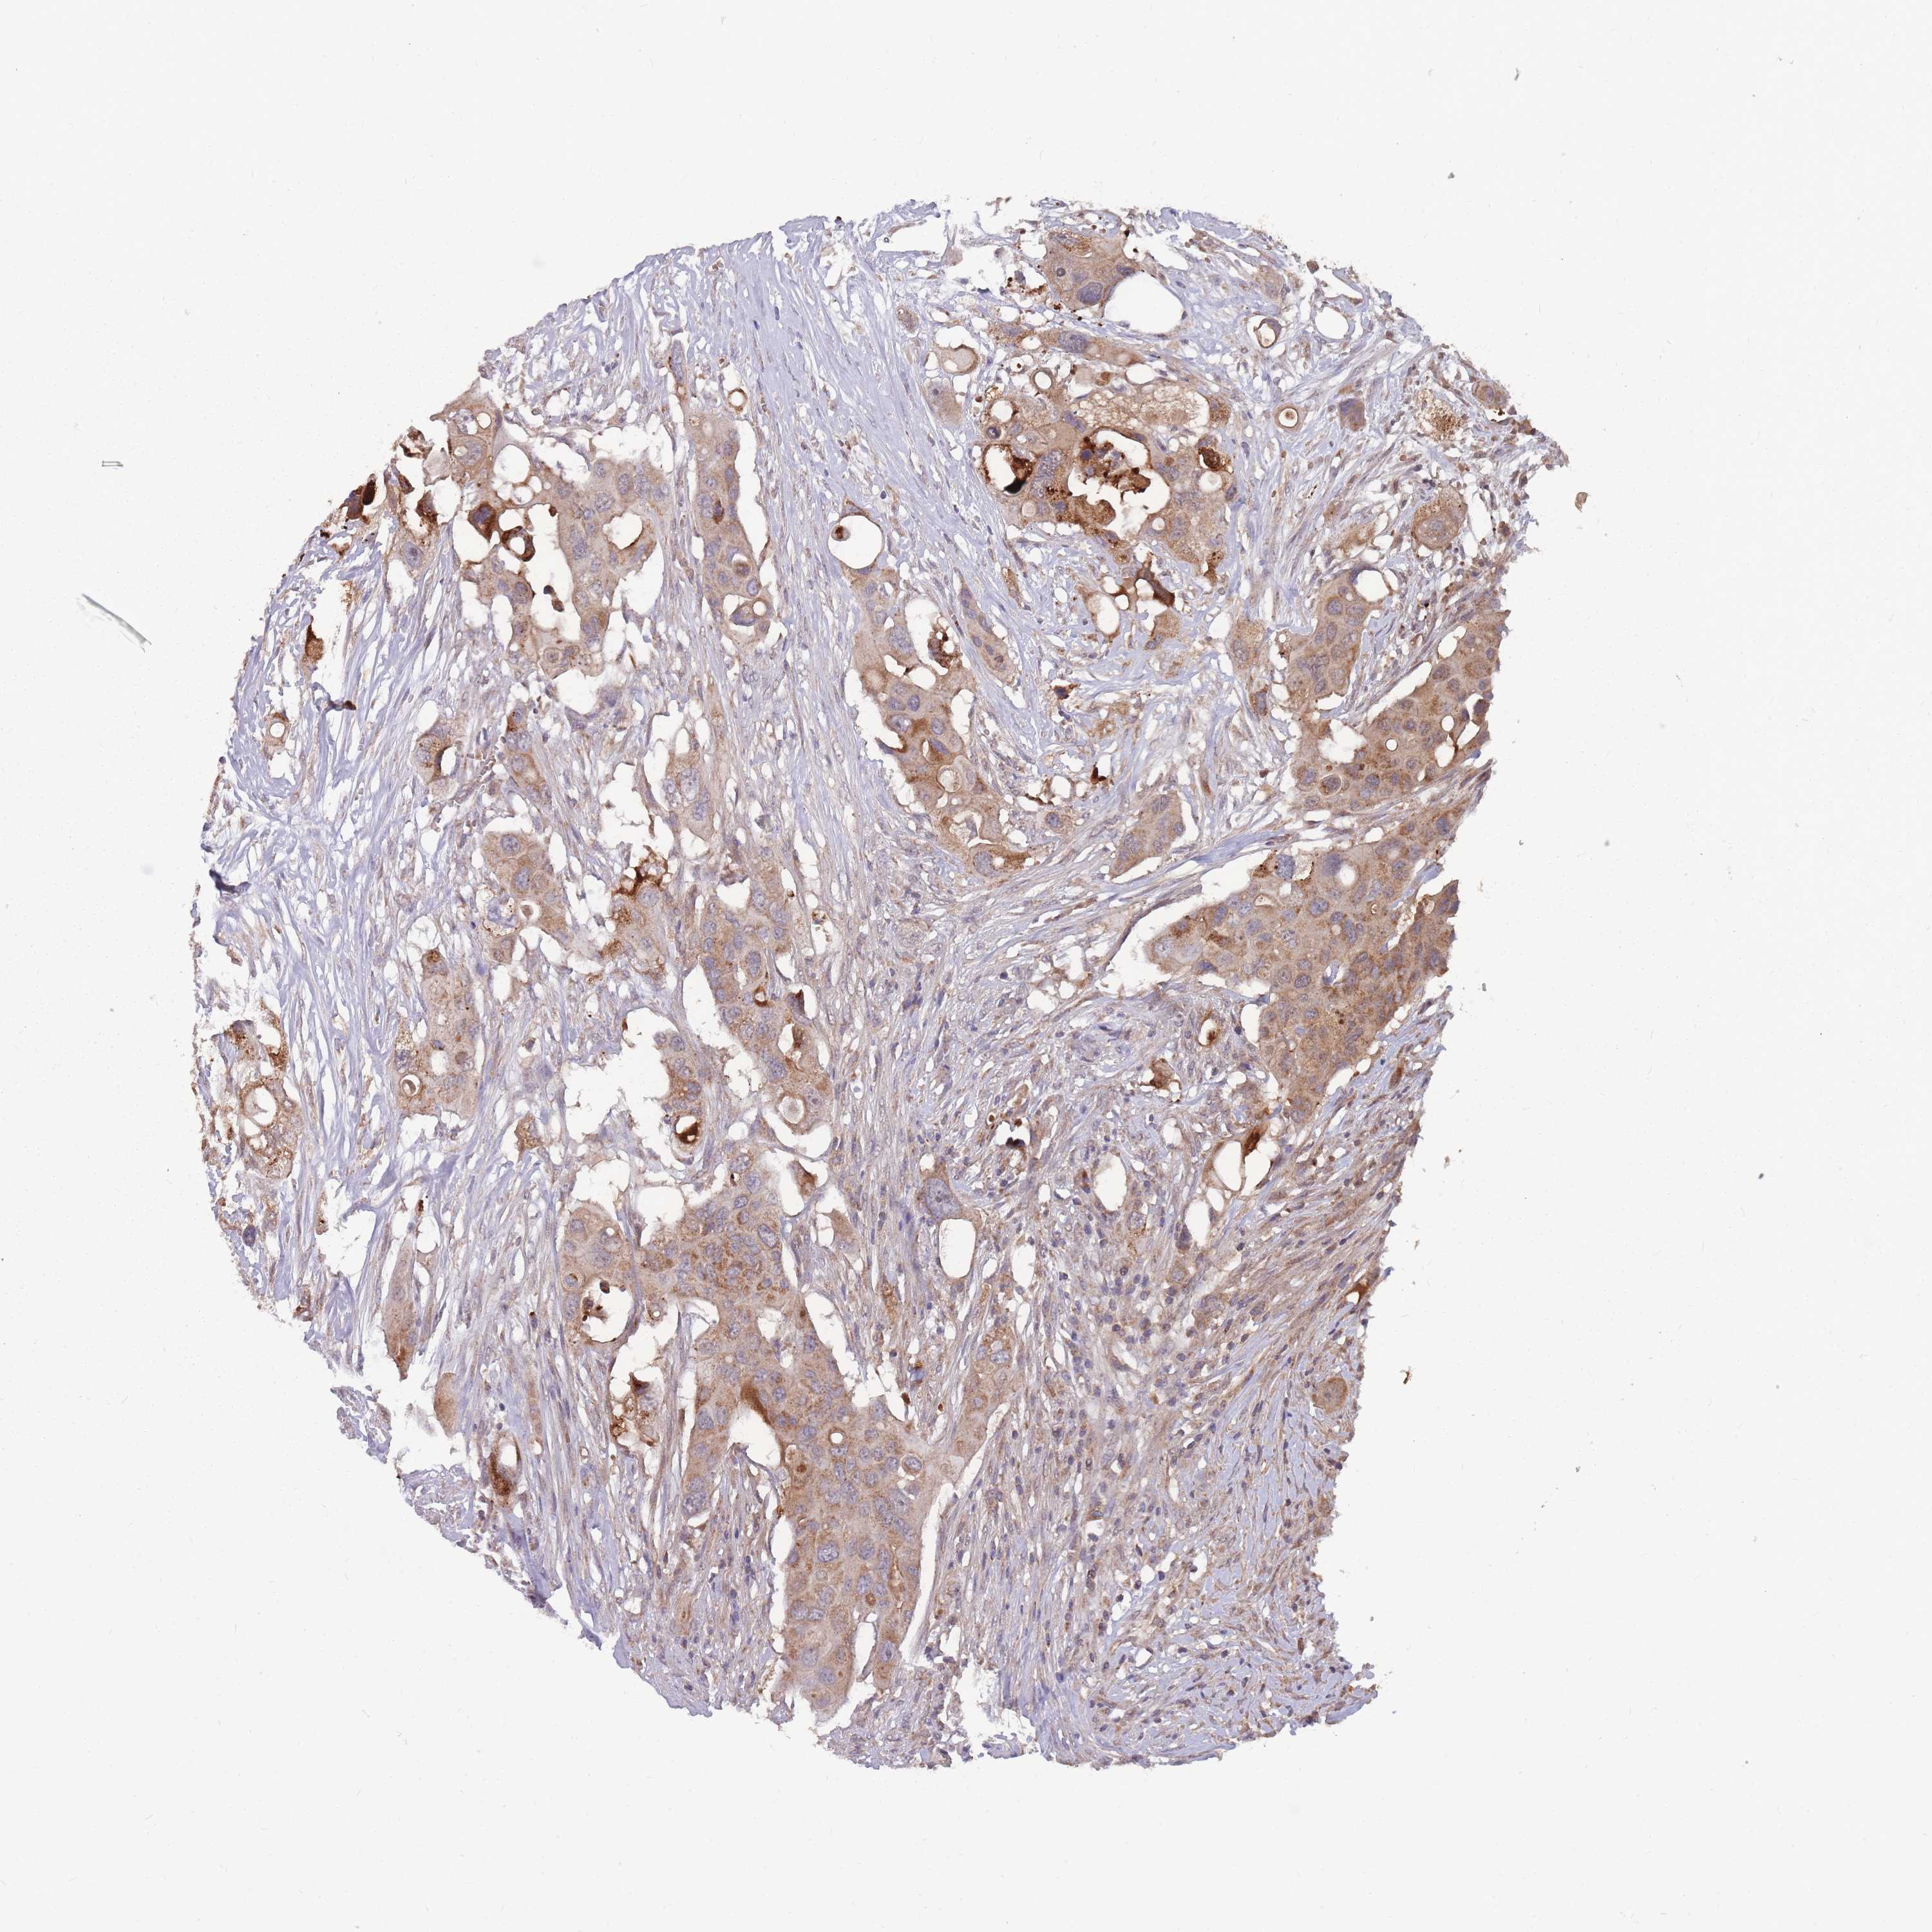

CANCER COLORECTAL CANCER Show tissue menu

ANTIBODIES

AND

VALIDATION